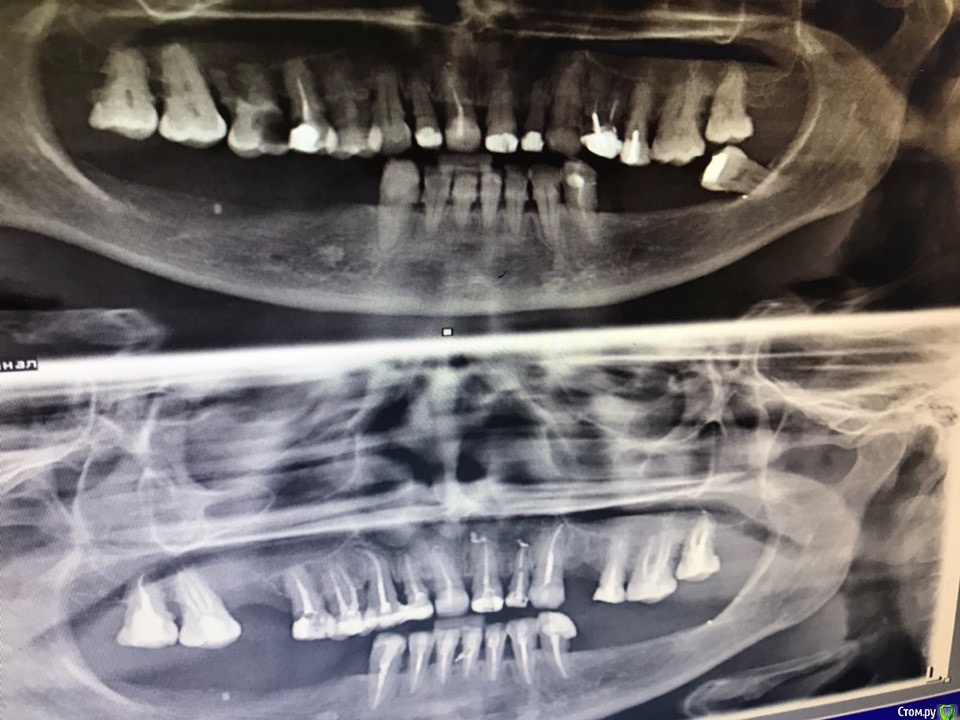

1586Doc Опубликовано 28 марта, 2019 Автор Поделиться Опубликовано 28 марта, 2019 Продолжение 2 Ссылка на комментарий

1586Doc Опубликовано 7 июня, 2019 Автор Поделиться Опубликовано 7 июня, 2019 все в кучу ) Ссылка на комментарий